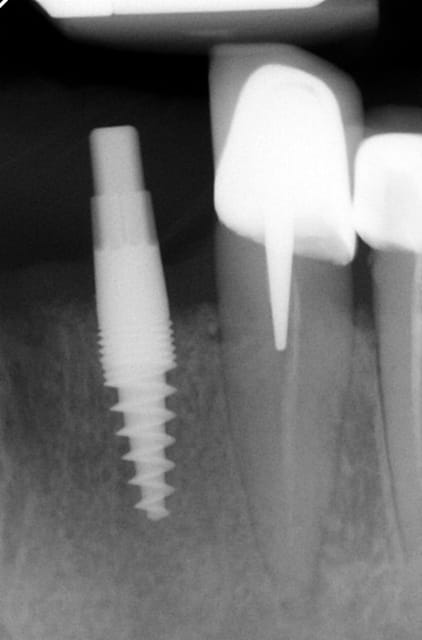

pour répondre à ta question : depuis 1994 , oui d ailleurs dans un des cas présentés tu as une radio après 10 ans :-)! (46 47 )

22  4 - Eugenol